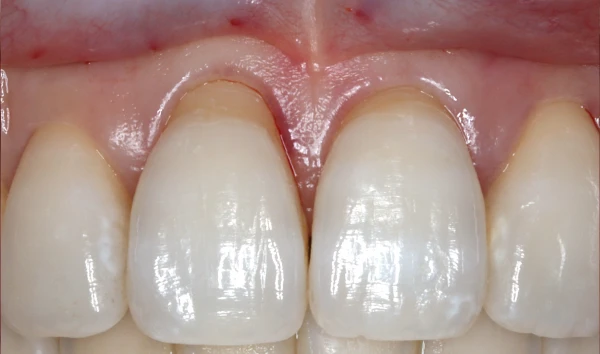

歯周組織再生療法

歯を残す最新治療

歯周病により破壊された、歯茎や骨を人工骨や成長因子などを用いて再生させる治療方法です。

将来的に抜歯となるリスクの高い歯などを歯周組織を再生させ、歯を長持ちさせることを目的とします。歯周病でダメになった歯をどうしても残したい方、歯ぐきや歯槽骨を元に戻して歯の寿命をしっかり伸ばしたい方に適応される治療方法です。 -